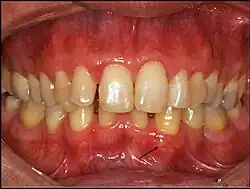

CGA (seta): observa-se pequena lesão de aspecto ligeiramente esbranquiçado próxima à raiz do canino inferior esquerdo.

CGA (seta): observa-se pequena lesão de aspecto ligeiramente transparente a esbranquiçado próxima à raiz do canino inferior esquerdo.

O cisto gengival do adulto tende a se apresentar como uma lesão nodular firme bem delimitada, com coloração normal, transparente ou tendendo ao azul-arroxeado, na mucosa gengival de adultos.[2] O cisto gengival do neonato é uma lesão nodular bem delimitada e esbranquiçada na mucosa alveolar de um recém-nascido.[3] Anteriormente, o CGN foi chamado de pérola de Epstein, ou nódulo de Bohn, mas essas nomenclaturas não são utilizadas atualmente por serem diferentes do CGN:[3]